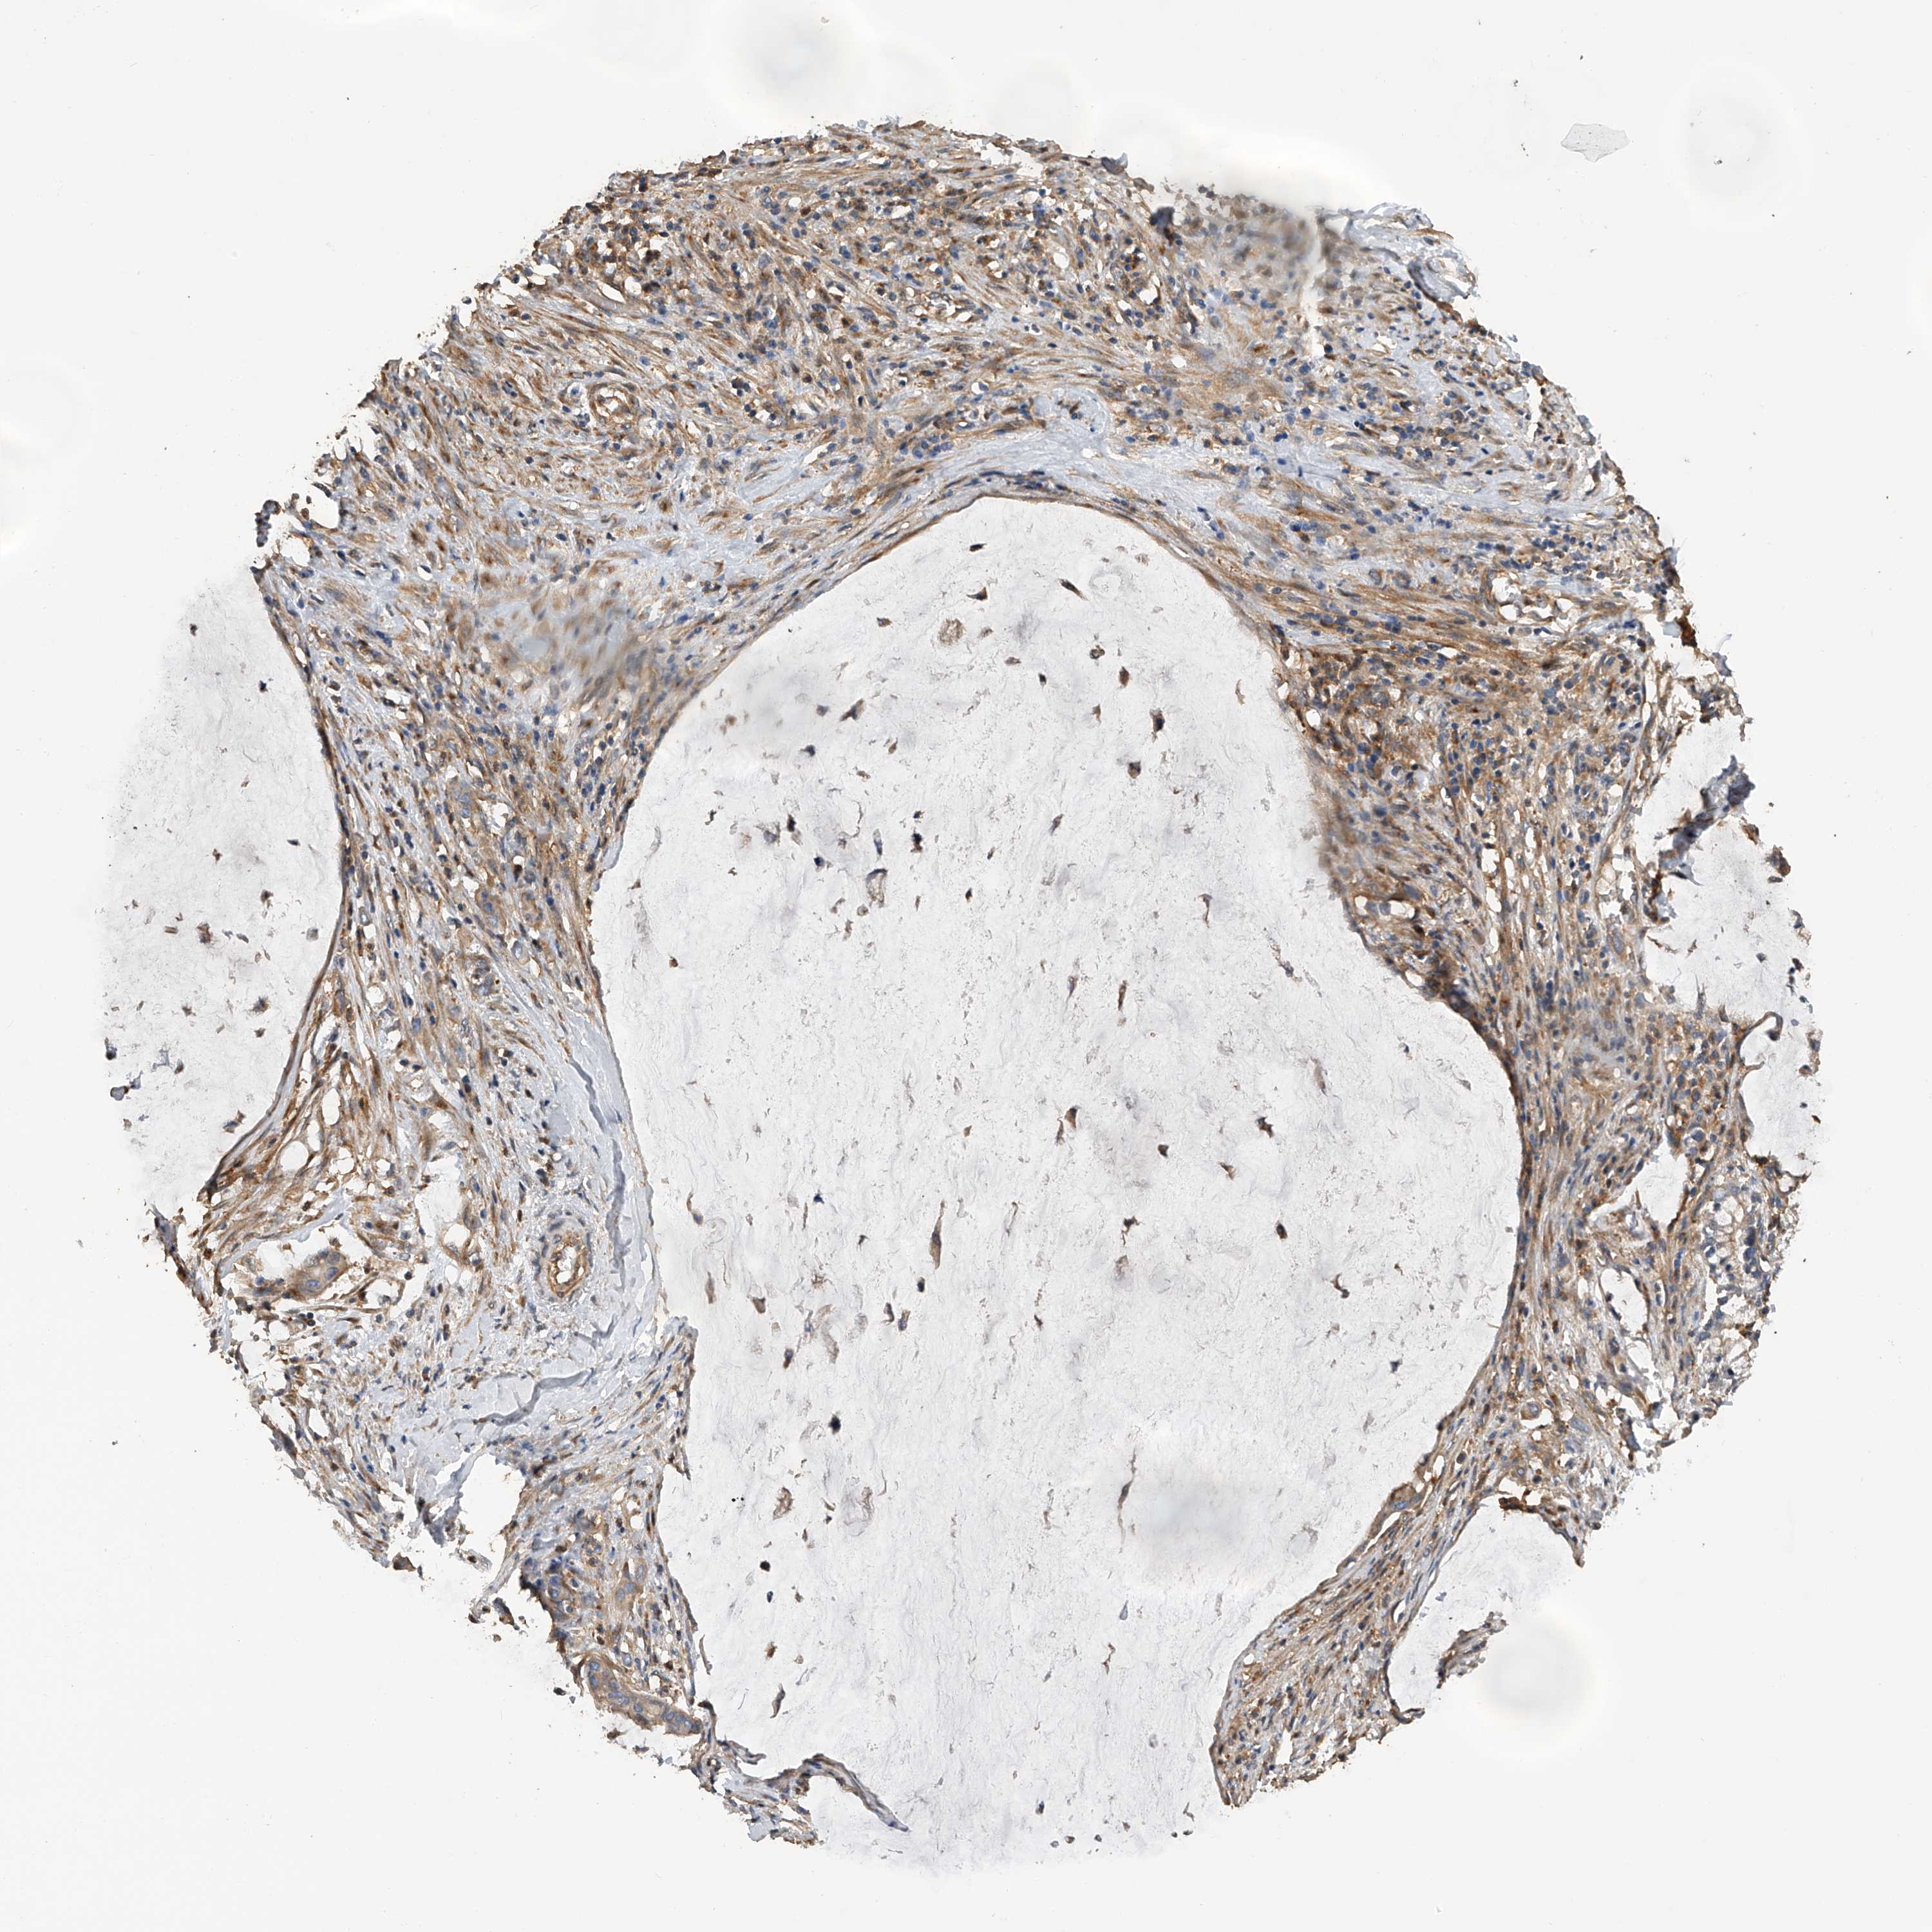

PANCREATIC CANCER - Protein expressioni

A mouse-over function shows sample information and annotation data. Click on an image to view it in a full screen mode. Samples can be filtered based on level of antibody staining by selecting one or several of the following categories: high, medium, low and not detected. The assay and annotation is described here.

Note that samples used for immunohistochemistry by the Human Protein Atlas do not correspond to samples in the TCGA dataset.

Antibody stainingi

Antibody staining in the annotated cell types in the current human tissue is reported as not detected, low, medium, or high, based on conventional immunohistochemistry profiling in selected tissues. This score is based on the combination of the staining intensity and fraction of stained cells.

Each image is clickable and will lead to virtual microscopy that enables deeper exploration of all samples and also displays staining intensity scores, fraction scores and subcellular localization as well as patient and tissue information for each sample.

Antibody HPA029412

Antibody CAB034366

Staining

High

Medium

Low

Not detected

Intensity

Strong

Moderate

Weak

Negative

Quantity

>75%

75%-25%

<25%

None

Location

Nuclear

Cytoplasmic/membranous

Cytoplasmic/membranous,nuclear

Adenocarcinoma, NOS